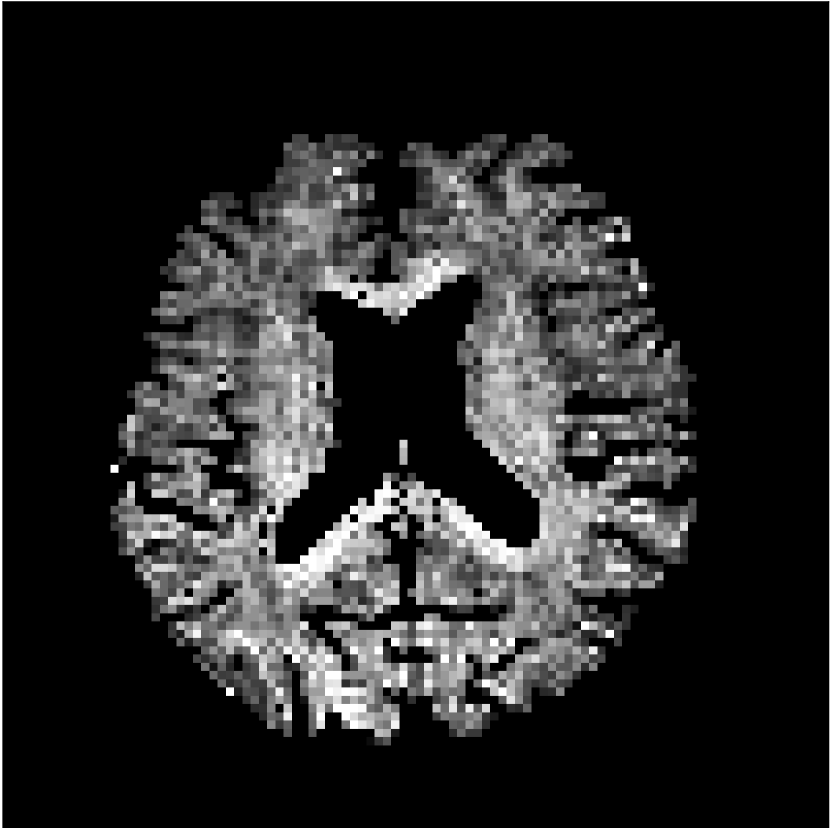

Figure 9 shows parameter maps for the different methods without partial Fourier (No PF) and with 5/8ths partial Fourier (5/8 PF). Mean diffusivities calculated from the raw DWI data (Raw) show notable noise and Gibbs ringing artifacts, while this is substantially removed with the state-of-the-art (SoA) method. However, the state-of-the-art method begins to lose its ability to compensate for the Gibbs ringing and resolution loss when partial Fourier is utilized in the acquisition. The effects of partial Fourier increases are primarily evident in the enlargement of the lateral ventricles and the presence of black lines in the vicinity of the lateral ventricles. The MCNN model is able to compensate somewhat for the ringing effects, but begins to introduce substantial artifacts at the 5/8ths partial Fourier factor, whereas the CCNN model continues to give high-quality mean parameter maps across all PF factors.

Raw

SoA

MCNN

Standard PF

CCNN

s/mm2

No PF

MD, m2/ms

5/8 PF

FA

MK

Similar trends are observed in the other diffusion parameter maps.